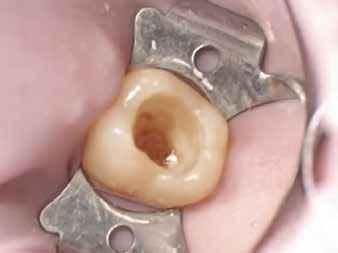

Egy 31 éves férfi páciens jelentkezett a jobb felső első molárisából kiinduló, reverzíbilis pulpitisre utaló tünetekkel. A klinikai vizsgálat során meglévő okkluzo-palatinális ezüsta-

malgám restauráció volt észlelhető, valamint szekunder caries mesiálian, a marginális gerinc kavitációjával együtt (10. ábra). A mesio-bukkális csücsök csúcsán kopási fazetta volt látható; a fog egyébként klinikailag és radiológiailag épnek bizonyult. A tájékoztatáson alapuló beleegyezést követően a kezelési terv II. osztályú, háromfelszínű direkt kompozit restauráció volt.

A szerző helyi érzéstelenítés után a fogat latexmentes kofferdámmal izolálta; a gumit befordította, és közben fogselyem segítségével interproximálisan visszahúzta (11. ábra)

Nagyítás alatt (operációs mikroszkóp) a régi restaurációt körte alakú gyémántfúróval távolította el, 1,5-es sebességfokozatú elektromos kézidarabbal kb. 45 000/ perc fordulatszámon vízhűtés mellett, így a mesiális oldalon feltárta a szuvasodást. A szerző az elektromos kézidarabot részesíti előnyben a nagy nyomaték és a kisebb, alacsonyabb sebességnél előforduló torpanási hajlam miatt. A szomszédos premoláris fogat ék (Triodent) segítségével védte az iatrogén sérülésektől (12. ábra). A szomszédos fog iatrogén sérülése jól dokumentált komplikációja a II. osztályú üreg dobozpreparációjának [18].

A cariest lépésről-lépésre távolította el, caries detektáló festék és a Peripheral-Seal koncepció [15] alkalmazásával, amely lehetővé teszi a magas kötőerejű, cariesmentes zománc- és dentinzóna kialakítását a kavitás peremén, miközben a mélyebben lévő, caries által érintett dentin megmarad remineralizáció céljából [16]. A preparáció szélét alumínium-oxid abrázióval kezelte a biofilm és az aprizmatikus zománc eltávolításának céljából, ezzel javítva a kötőerőt [17]; majd karbidfúrókkal elsimította, hogy eltávolítsa a mikroszkopikus szinten törött zománcprizmákat, így csökkentve a „Enamel Peel”-ből eredő fehér vonalak kialakulásának kockázatát (13. ábra) [18].

A fogat 37%-os foszforsavval kondícionálta, majd egy 4. generációs dentin bondot (Optibond FL, Kerr) alkalmazott. A II. osztályú dobozt először centripetálisan zárta [19], folyékony és melegített kompozit kombinációjával, szekciós matrica segítségével.

A dentint hiperkróm, közepes opacitású pasztakompozittal modellezte, amely optikai tulajdonságaiban utánozza a természetes dentint (14. ábra). A barázdarendszerbe okker árnyalatú színezőanyagot vitt fel a restauráció színintenzitásának fokozása érdekében (15. ábra).

Ezután közepes transzlucenciájú, zománcszínű kompozitot helyezett a kavitásba, az okkluzális iránytű technika alkalmazásával. Külsőleg sötétbarna színezést vitt fel a barázdák elszíneződésének imitálására (16. ábra).